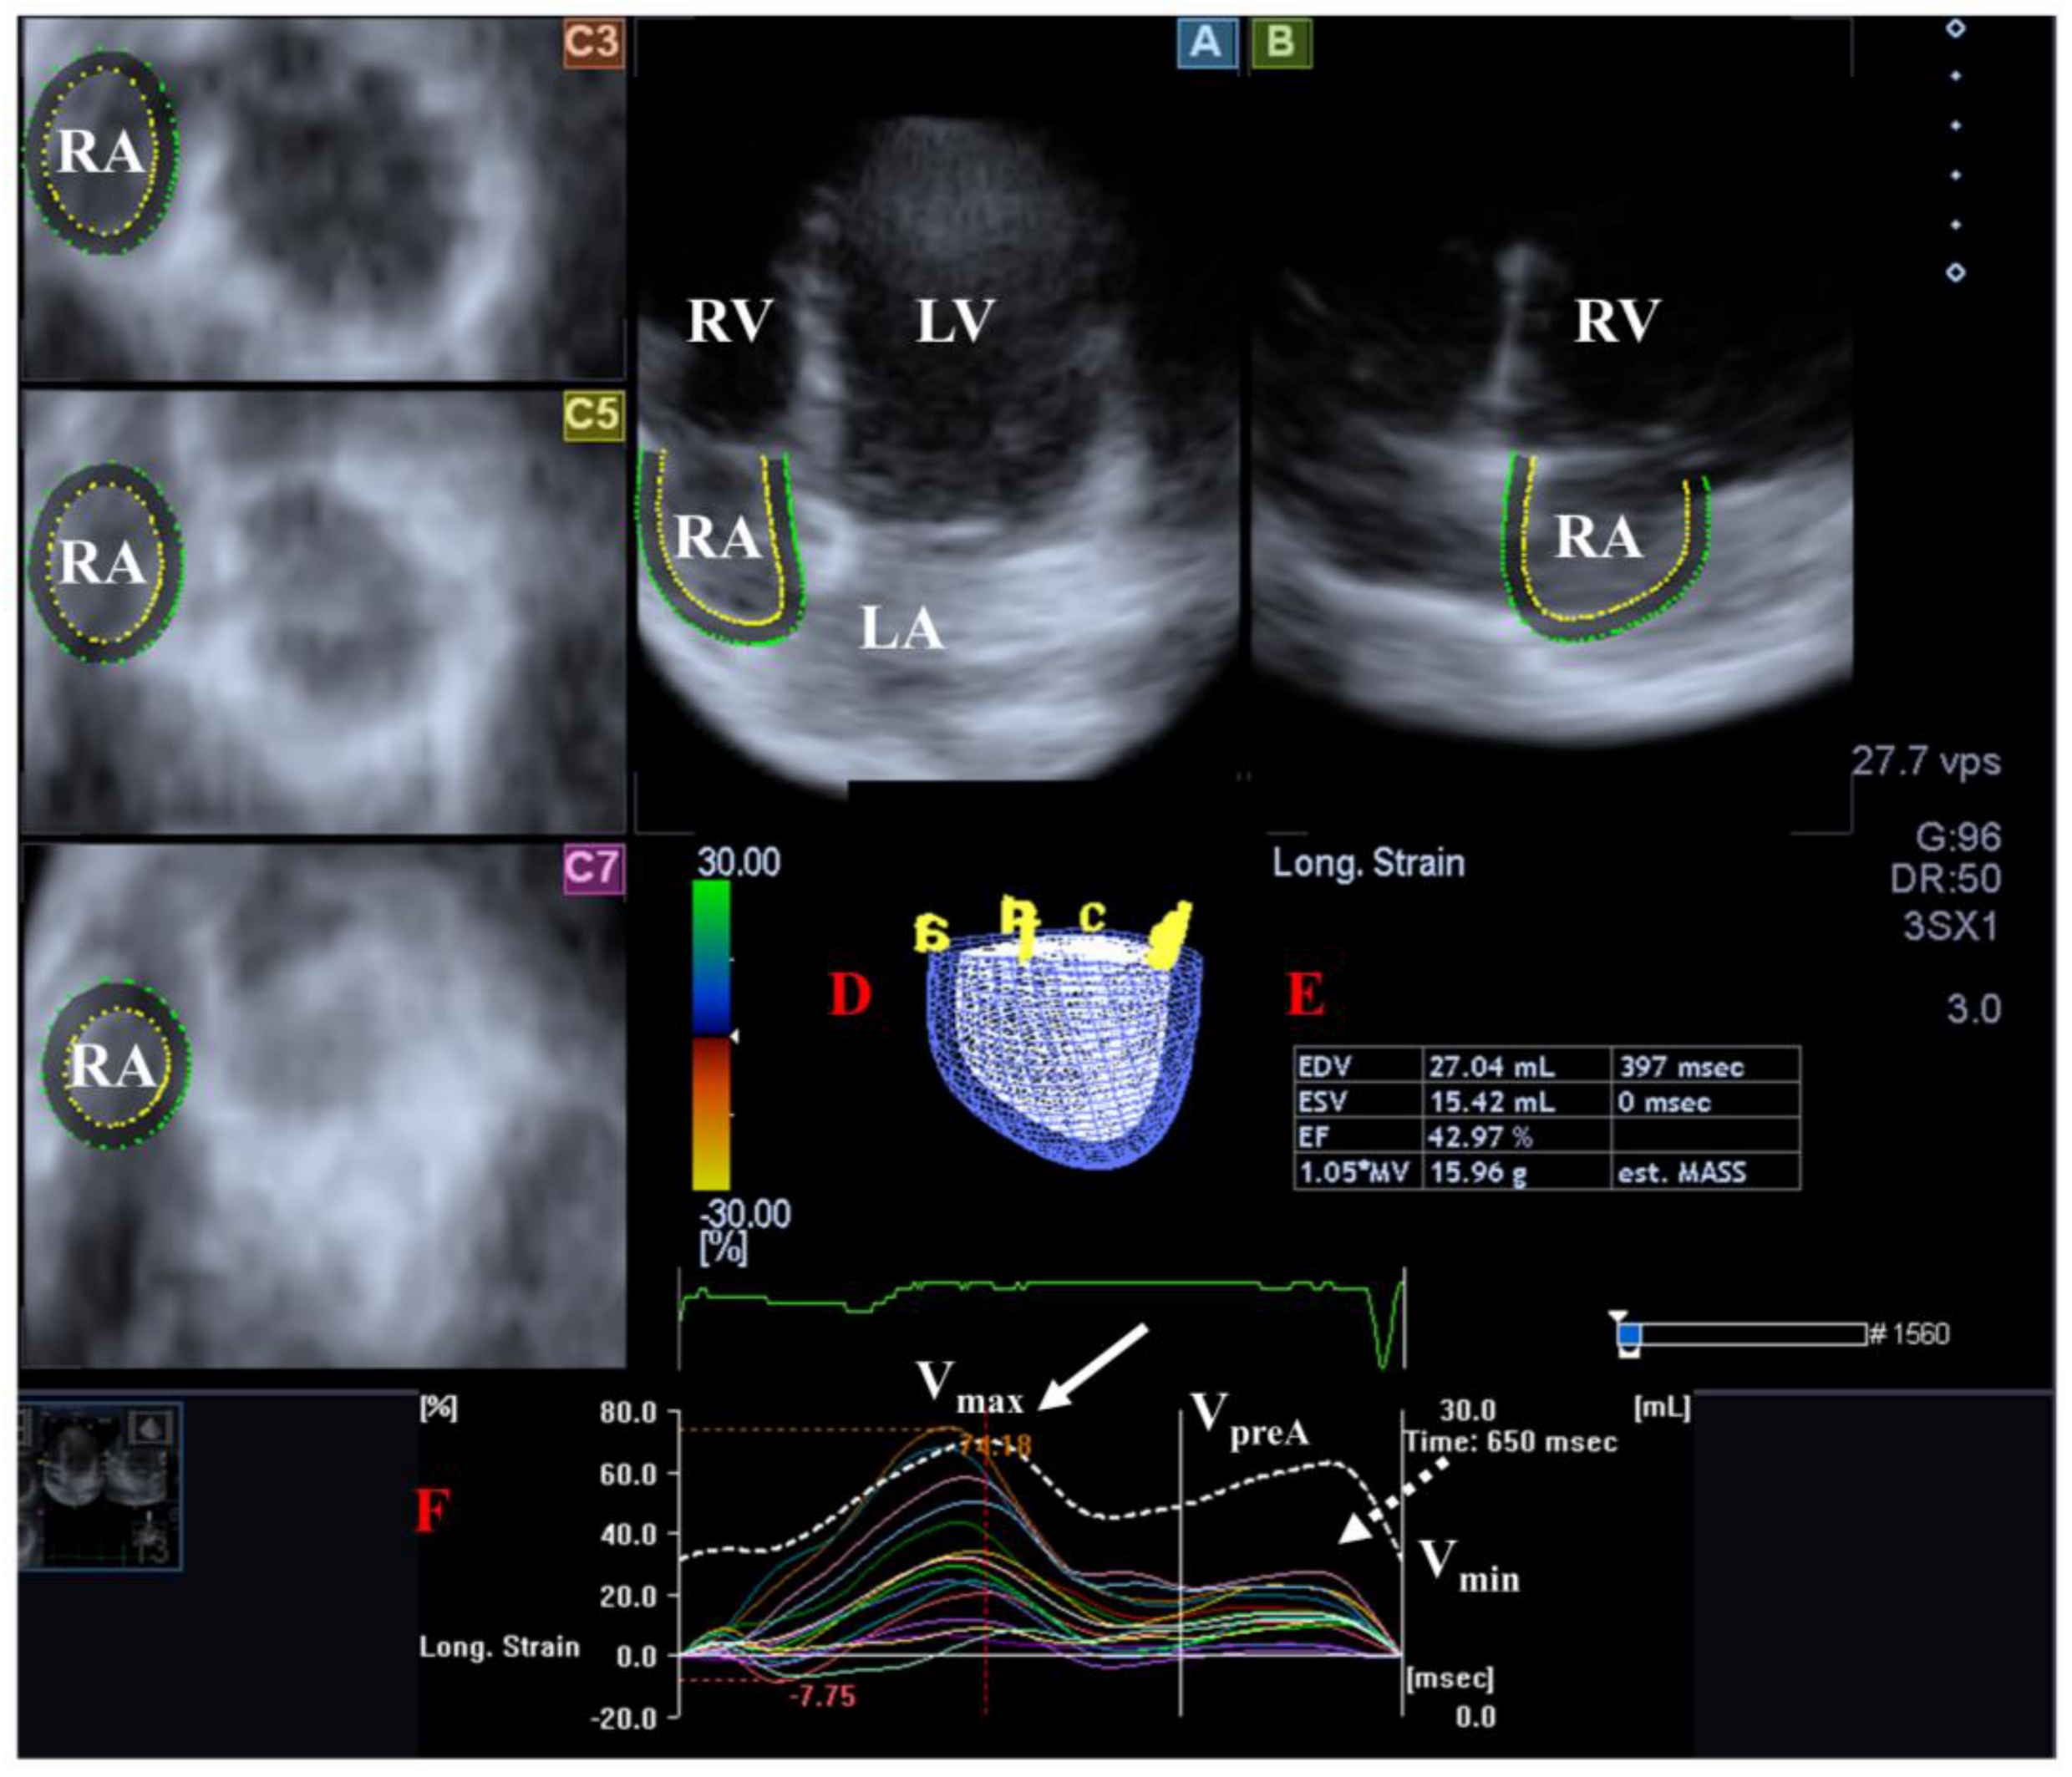

The RA is composed of three components: the venous part, the appendage and the vestibule. The muscle fibers of the RA run in circumferential and longitudinal directions. There are several phases of RA function including reservoir [in systole, its volume is highest], conduit [in early diastole] and booster pump [in late diastole, its volume is lowest]. Additionally, RA has a regulator role in the conduction of the heart via the sinus node which is located in its wall and also produces atrial natriuretic peptides regulated by tension and baroreceptors [102] (Figure 4).

Figure 4.

Examination of the right atrium (RA) by three-dimensional (3D) speckle-tracking echocardiography. Following echocardiographic data acquisitions, the following typical views are created: (A) Apical 4-chamber and (B) two-chamber longitudinal views and (C3,C5,C7) cross-sectional views at basal, midatrial and superior levels, respectively. RA can be easily detected alongside other heart cavities including the left ventricle (LV) and atrium (LA) and the right ventricle (RV). A number of other details were also presented including (D) 3D cast and (E,F) maximum (Vmax), preatrial contraction (VpreA) and minimum (Vmin) volumes of the RA and curves representing changes in volumes and strains of _RA over time. Reservoir (peak) and active contraction RA strains are represented by white and dashed white arrows, respectively.